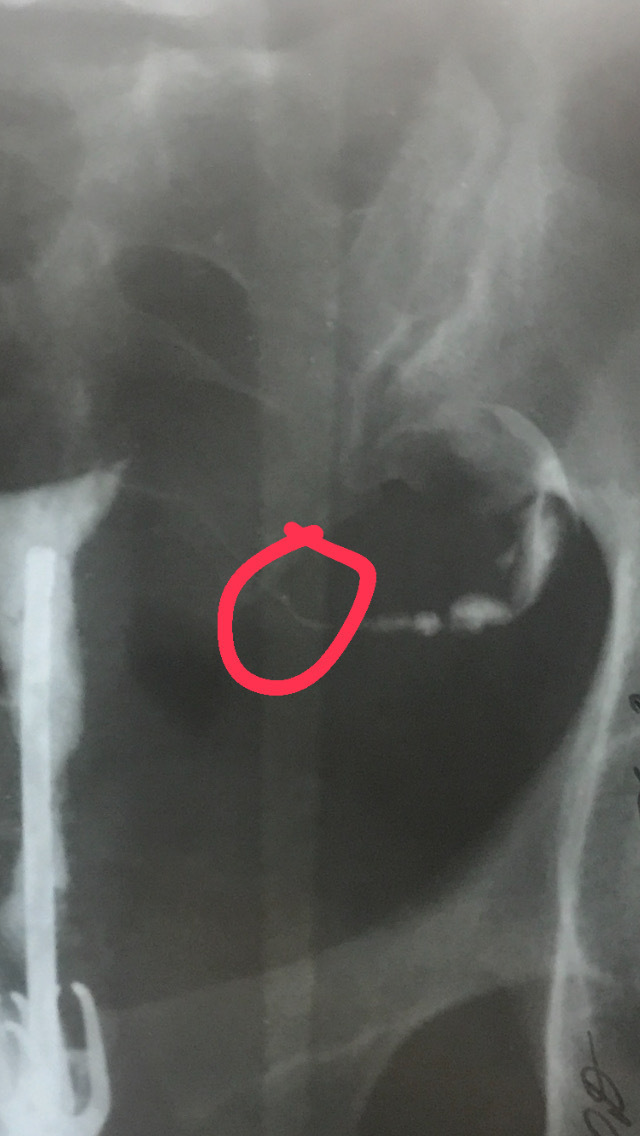

2. УЗИ органов малого таза (молочных желёз и ММГ также есть в этой рубрике, но скорее как обязательное ежегодное исследование - к СПКЯ мы это не привязываем.)

Обращаемся к клиническим рекомендациям: для диагностики поликистозных яичников (ПКЯ), необходимо наличие в яичнике 12 и более фолликулов, имеющих диаметр 2-9 мм и/или увеличение овариального объема более 10 мл. Увеличение овариального объема считается более надежным критерием диагностики СПКЯ, чем количество фолликулов!